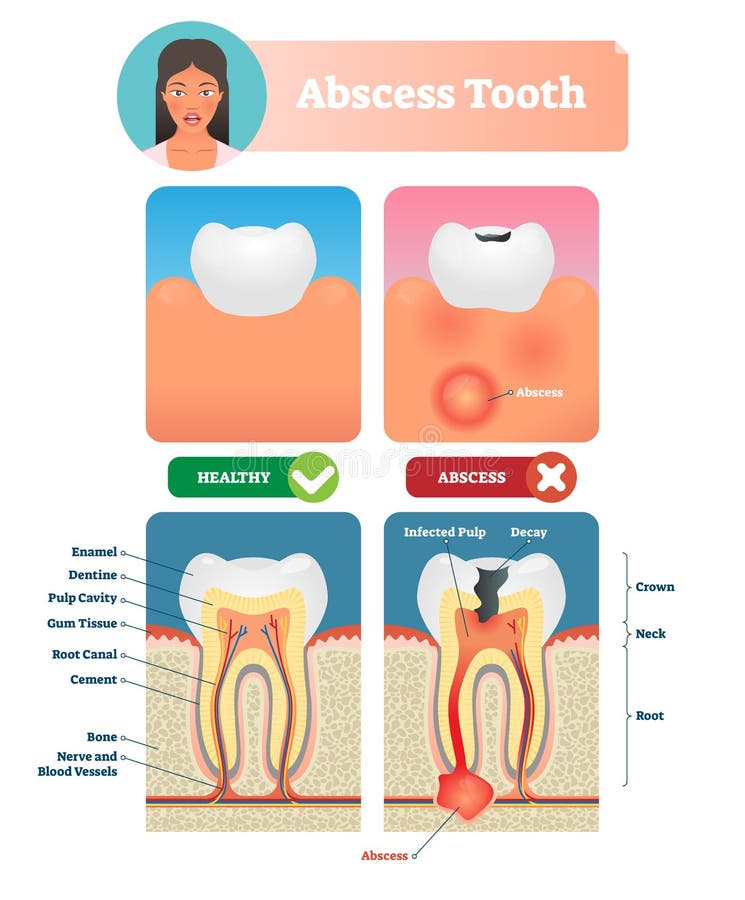

Tanden strukturerar Medicinskt diagram av strukturen av det inre tvärsnittet av tanden